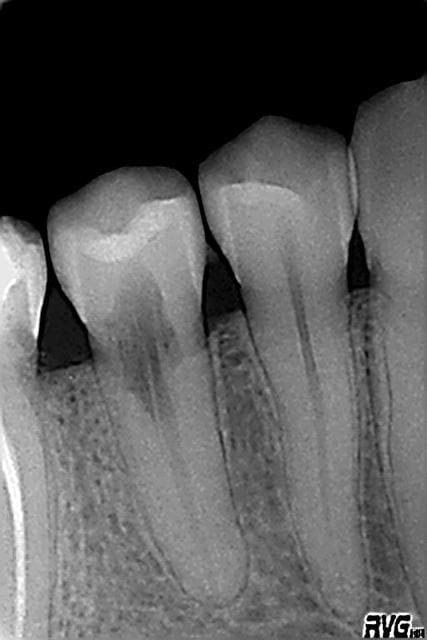

Pronostics...?